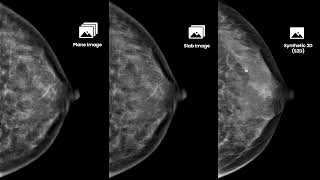

Aidia Luxe 3D Tomosynthesis, Reimaging Excellence In Breast Imaging With Precision

Aidia, New Standard In Premium Digital Mammography L Drtech